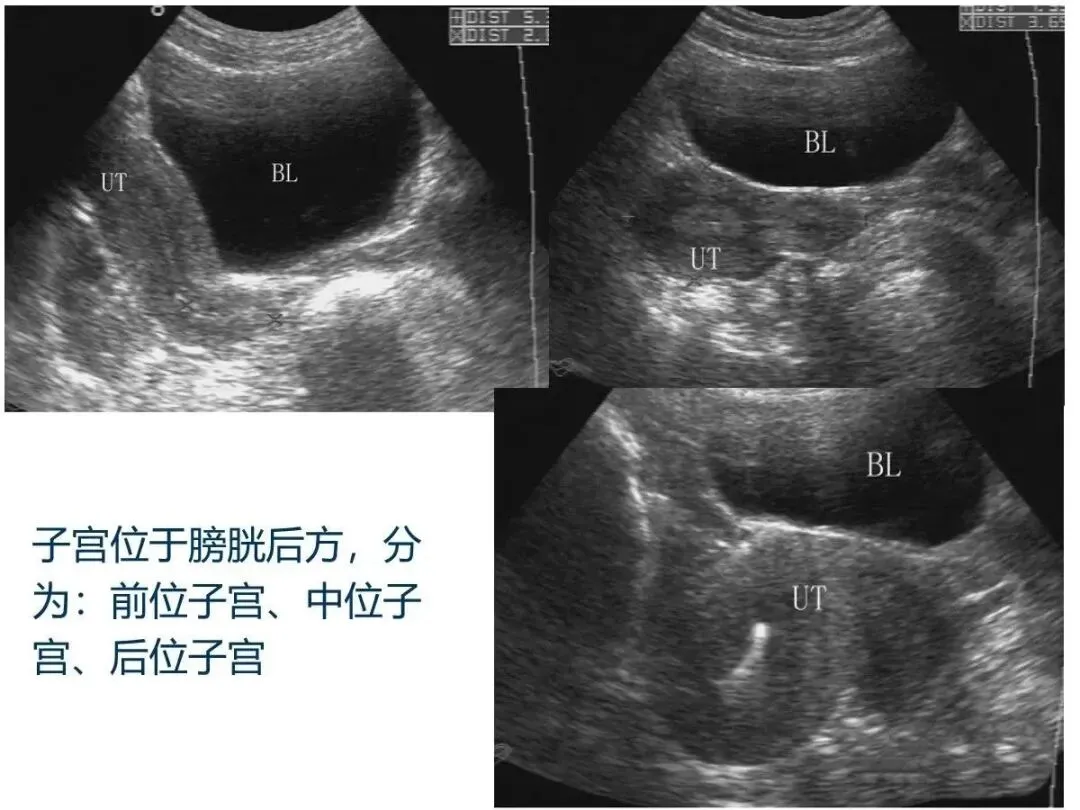

经腹耻骨联合上纵切

取仰卧位,将探头纵置于耻骨联合上缘,探头的前端对应人体的头侧,声束指向腹后方。

经腹耻骨联合上横切

取仰卧位,将探头横置于耻骨联合上 缘,探头的前端对应人体的右侧,声束指向腹后方。